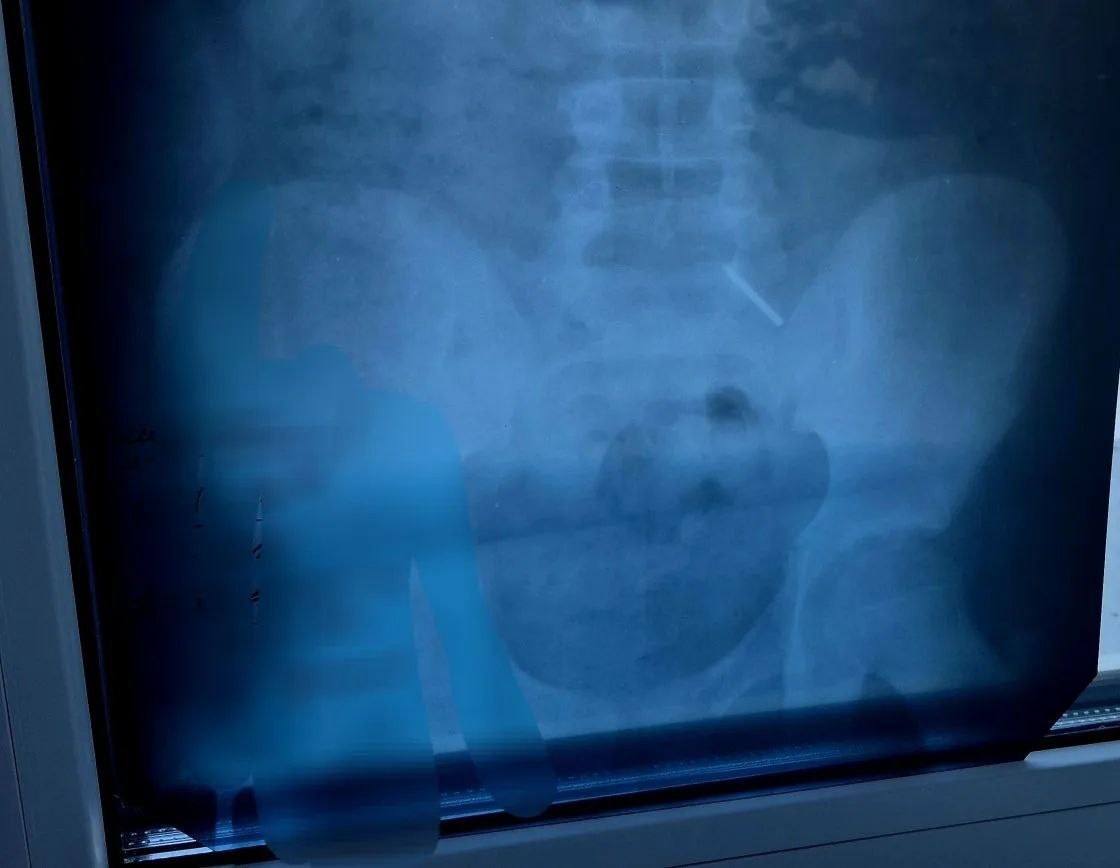

Как рассказала детский хирург Дарья Гусева, из-за позднего обращения за помощью достать предмет с помощью эндоскопа не удалось. Основной задачей врачей стало предотвратить повреждение кишечника и внутреннее кровотечение. Ребенка тщательно наблюдали, делали контрольные рентгеновские снимки.